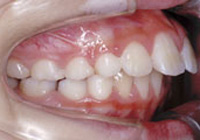

症例4:上顎前突(出っ歯)

治療前

治療後